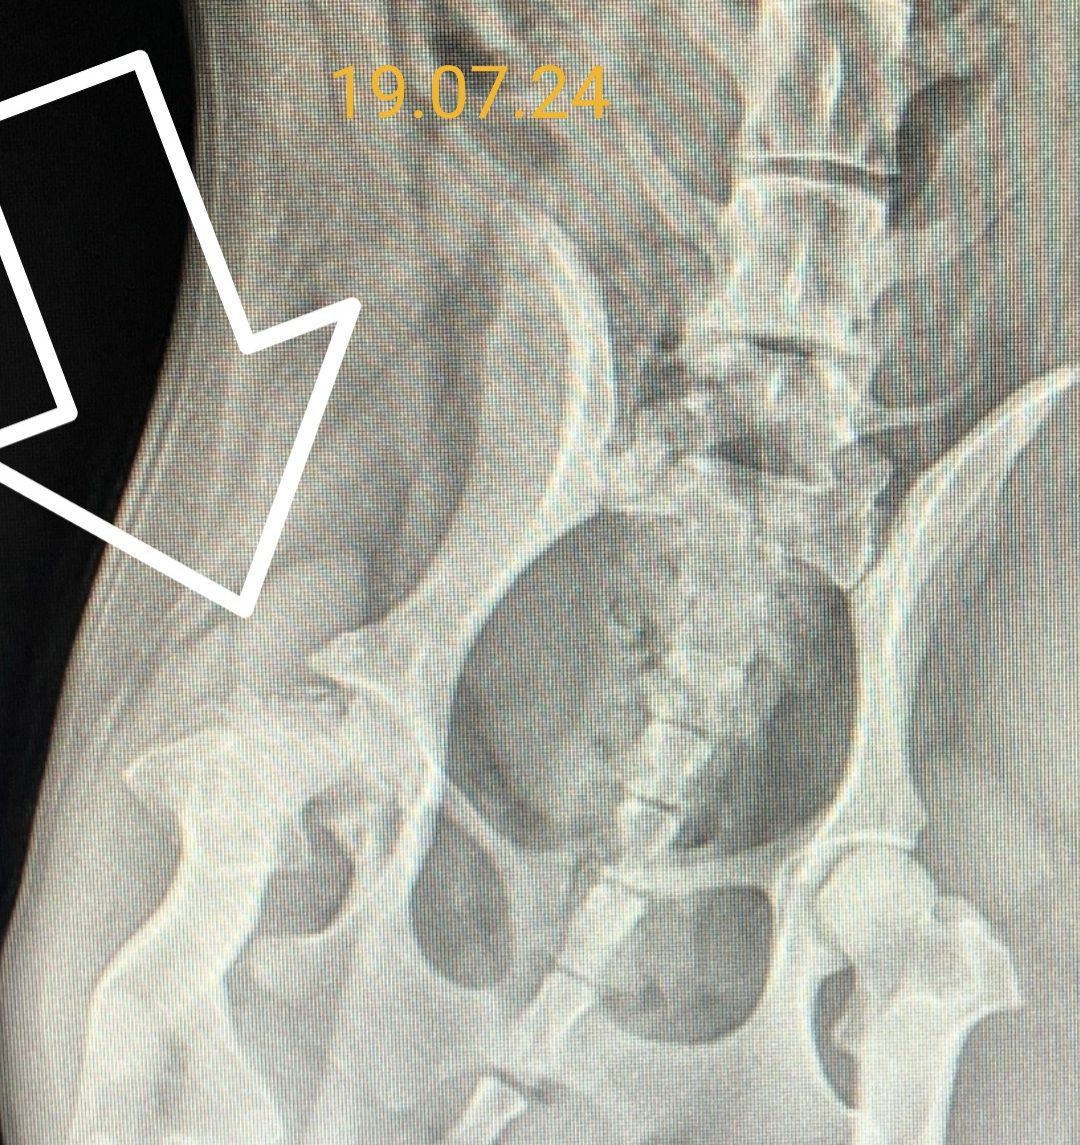

19.07.24 Rg. Praxis Wolf Röntgen, Diagnose, Blutabnahme für OP, etc. 182,82 €

Termin in der Praxis Wolf. Schon beim Abtasten fühlt er Unebenheiten am Becken und sie zeigt dort Schmerzen. Die Röntgenaufnahme zeigt, dass der Knochenkopf defekt ist. Lt. TA eine alte Verletzung, die nichts mit dem Sprung zu tun hat. Es zeigt sich nämlich schon Knorpelbildung. Damit Polly noch ein wenig "ankommen" kann wird als OP-Termin der 05.08. vereinbart.